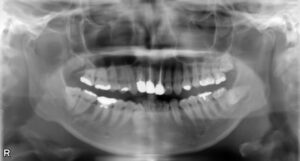

インプラント治療を成功させるうえで重要なのは、精密な治療計画です。そのためには顎の骨の状態を精密に把握する必要があります。そこで活躍するのが歯科用CTです。これまでのレントゲン検査とはくらべものにならないほどの詳細な情報を立体画像で確認することができます。

顎の骨の骨密度や厚み、さらに神経や血管の位置まで把握できるので、どの位置にどの角度でどれくらいの深さにどの種類のインプラントを埋入すればいいのかの綿密なシミュレーションが可能です。